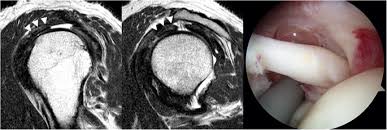

Estimate the cost of your mri or ct scan at american health imaging with our simple calculator. $800 pesos ($43.24 usd) mri of lumbar spine without dye: Super angebote für mri procedure hier im preisvergleich. Rotator cuff tears can often be diagnosed by physical examination, but cannot be confirmed without imaging. A mri in salt lake city costs $890 on average when you take the median of the 17 medical providers who perform mri procedures in salt lake city, ut. Average prices are for mri procedures performed at honorhealth facilities around the valley, and do not include physicians' fees. When i called one facility, they told me the mri i described would cost $1,600. In different conditions, the cost for even just one mri scan can surpass $13,000. They can range from $300 to $9000. Mri spine cervical w/o cont. I went to my gp after about 6 weeks of shoulder pain who said i'd torn something in my shoulder & referred me to physio, who i saw today. Please contact your physician's office and health insurance provider directly for price information. Our experienced staff are friendly and approachable, and can answer any.

Estimate the cost of your mri or ct scan at american health imaging with our simple calculator. Please contact your physician's office and health insurance provider directly for price information. How much does an mri cost? If patients have not hit their deductible, that money comes straight. Surgeries / operations (head & torso) The cost of an mri will vary greatly between inpatientand outpatient facilities. How much does an mri cost? Those on high deductible health plans or without insurance can save when they buy their procedure upfront through mdsave. Although they may not say so, some physicians in health care systems or hospital groups are contracted with hospitals. If a person receives an mri scan at the. Our experienced staff are friendly and approachable, and can answer any. A shoulder mri is done to check a shoulder for arthritis, bone tumors, torn ligaments or tendons, and other similar problems. Read more about how mdsave works.

Average prices are for mri procedures performed at honorhealth facilities around the valley, and do not include physicians' fees. I went to my gp after about 6 weeks of shoulder pain who said i'd torn something in my shoulder & referred me to physio, who i saw today. How much does an mri cost? What conditions does it treat? Super angebote für mri procedure hier im preisvergleich. On mdsave, the cost of a mri/ct with arthrogram ranges from $825 to $2,773. Please contact your physician's office and health insurance provider directly for price information. How much does a mri/ct with arthrogram cost? Rotator cuff tears can often be diagnosed by physical examination, but cannot be confirmed without imaging. How much does an mri cost? $9,082 pesos ($490.91 usd) total actual cost (mexico): These different factors contribute to the cost of the scan, but in general, an mri's cost can range from as low as $400 upwards to $3500. $800 pesos ($43.24 usd) mri of lumbar spine without dye: